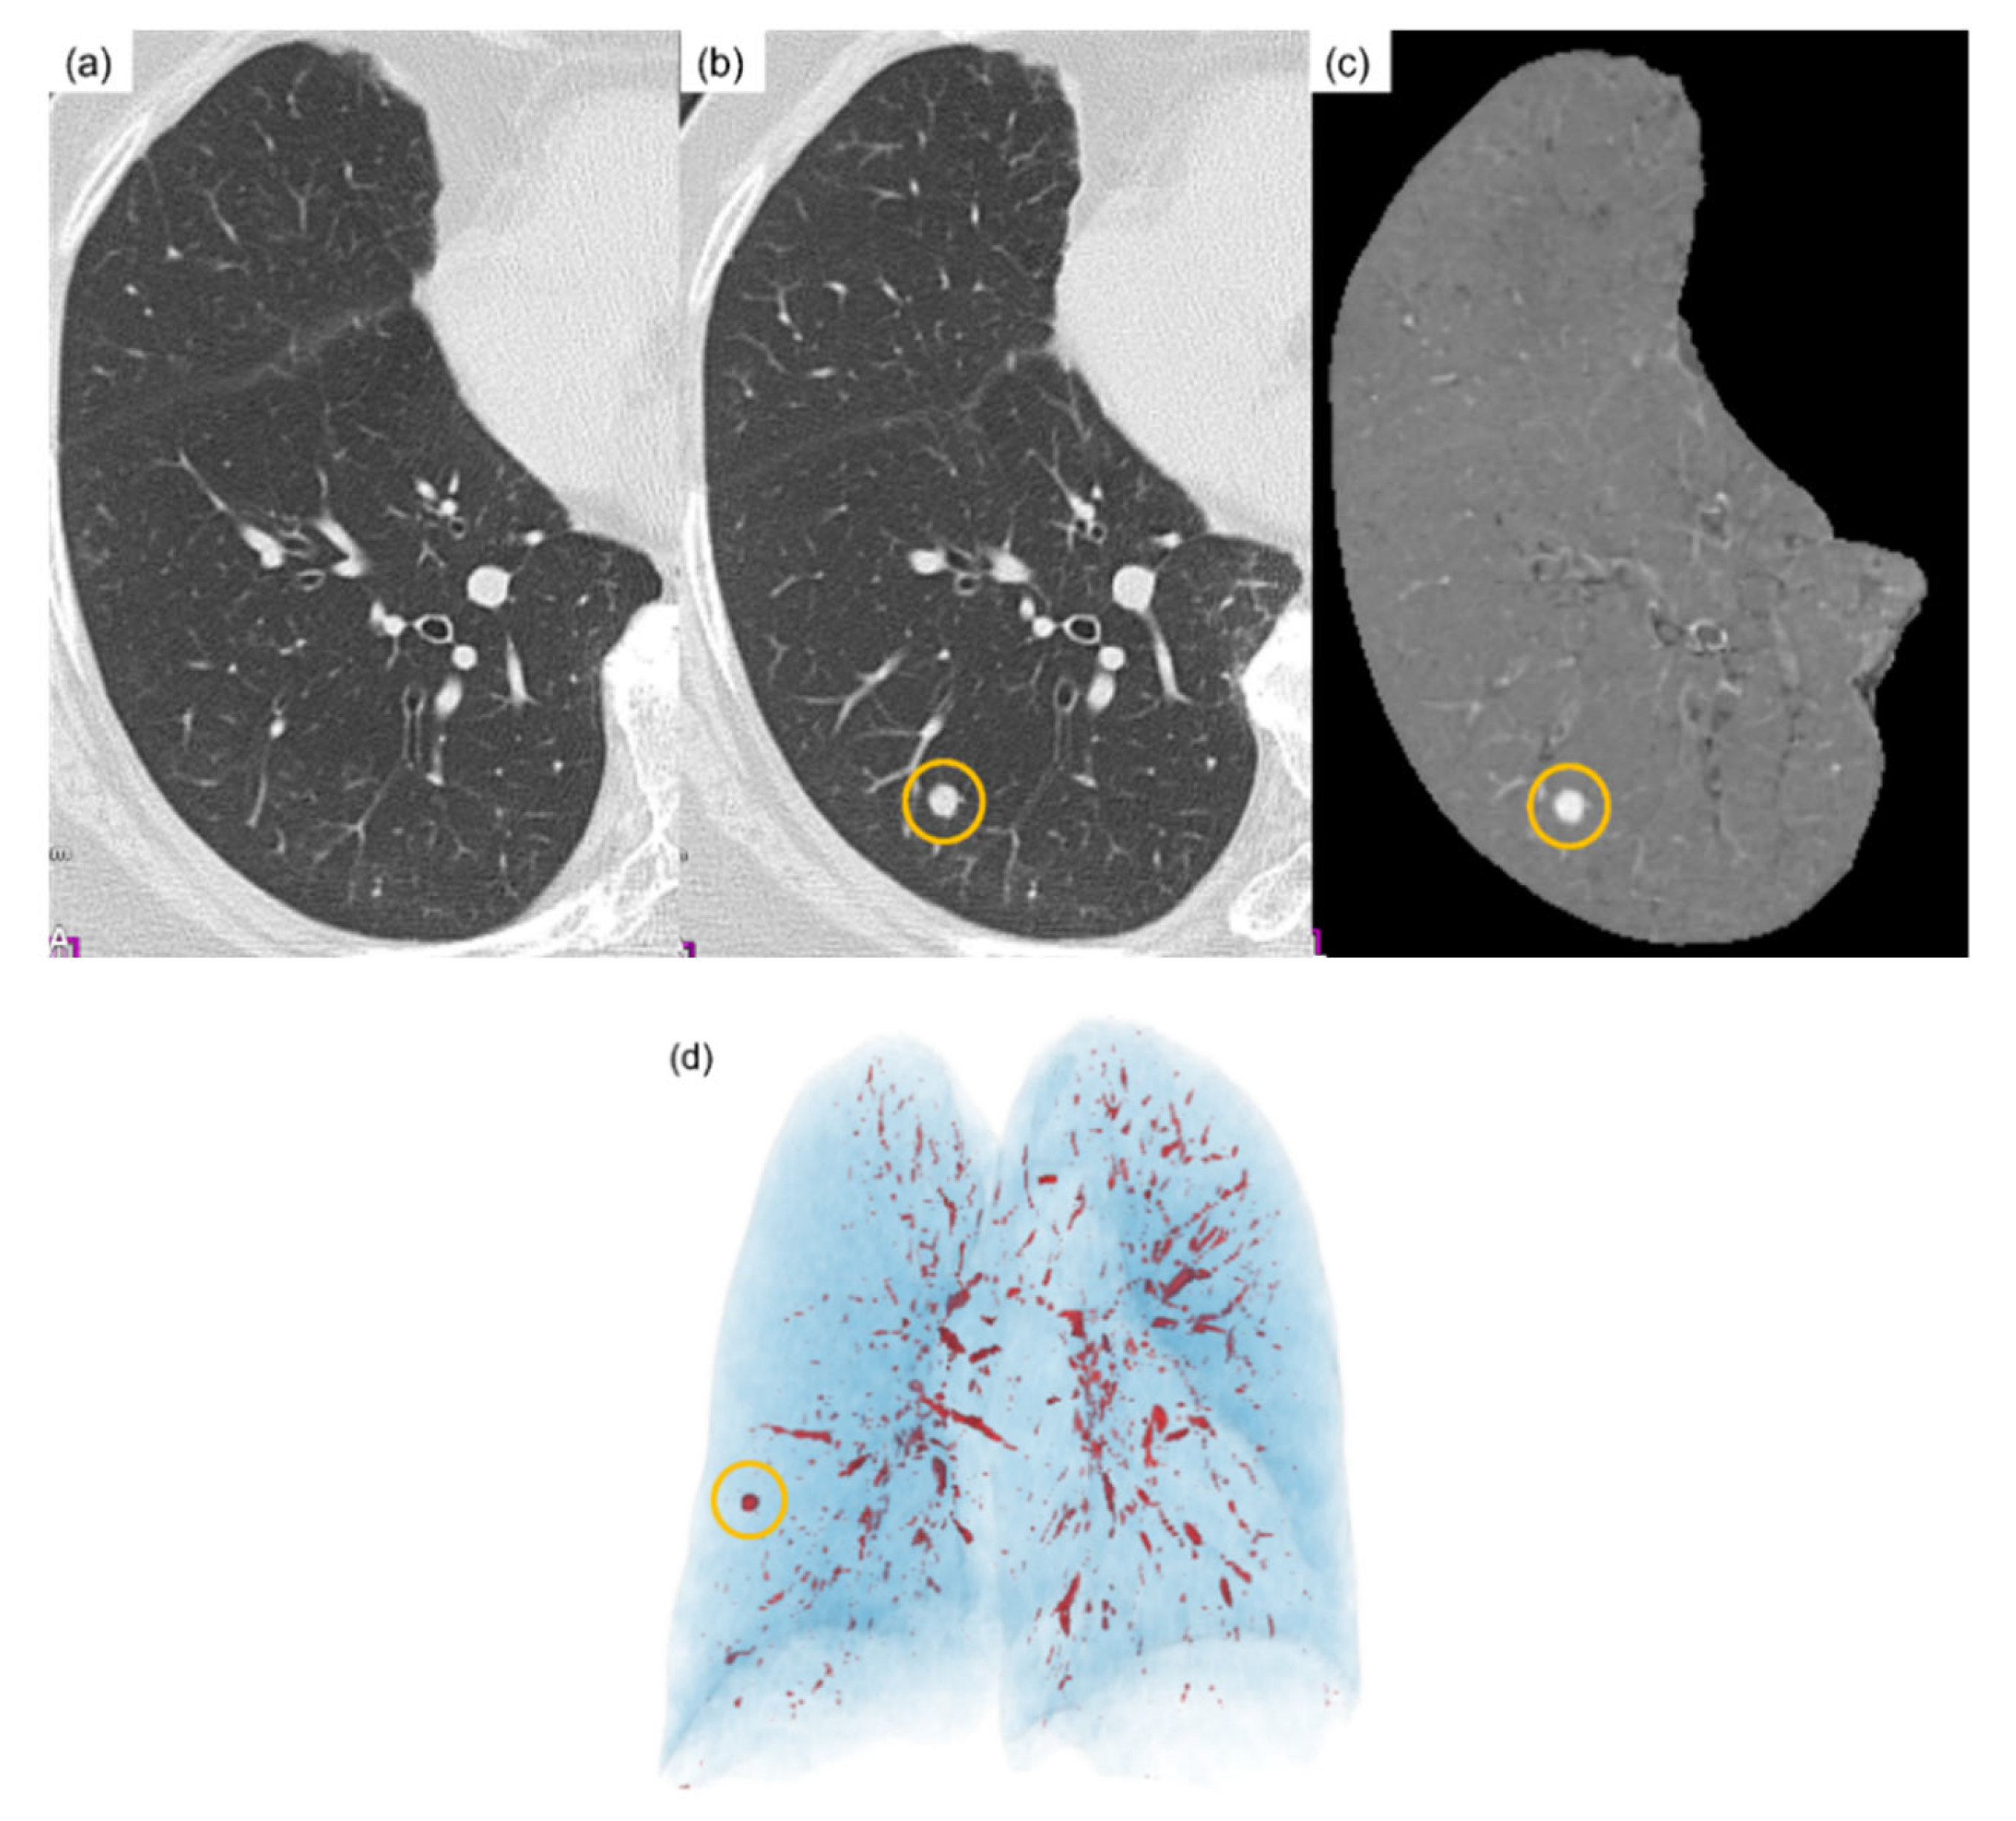

3.1. Temporal Subtraction Technique with Deep Neural Network

4.2. Results and Evaluation